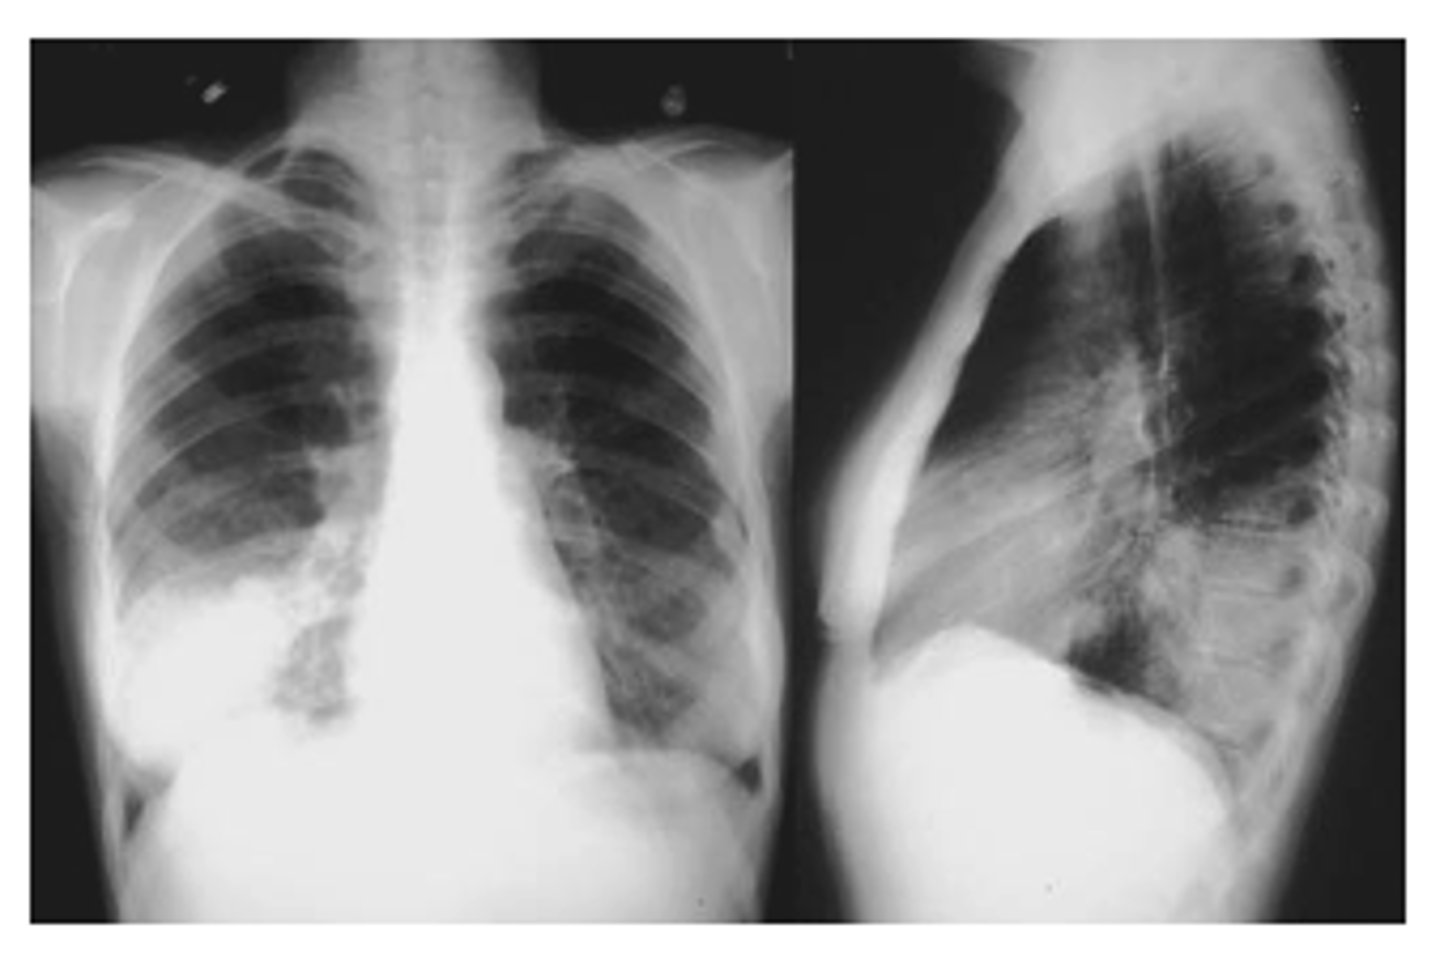

ID sign on back and finding

RML pneumonia obscuring the cardiac border but not the R hemidiaphragm. Note the triangular density on the lateral view.

<p>RML pneumonia obscuring the cardiac border but not the R hemidiaphragm. Note the triangular density on the lateral view.</p>